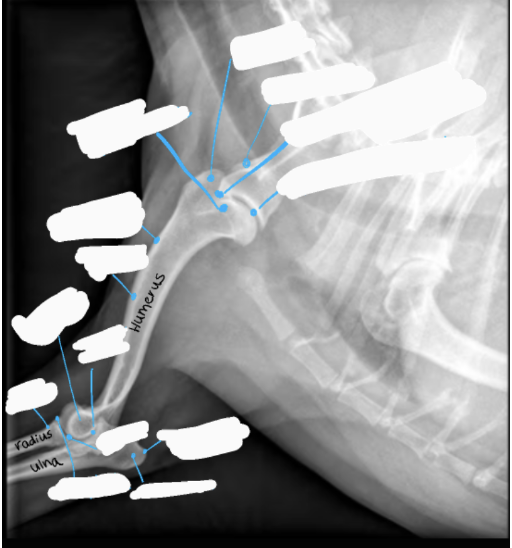

Q

Label the image